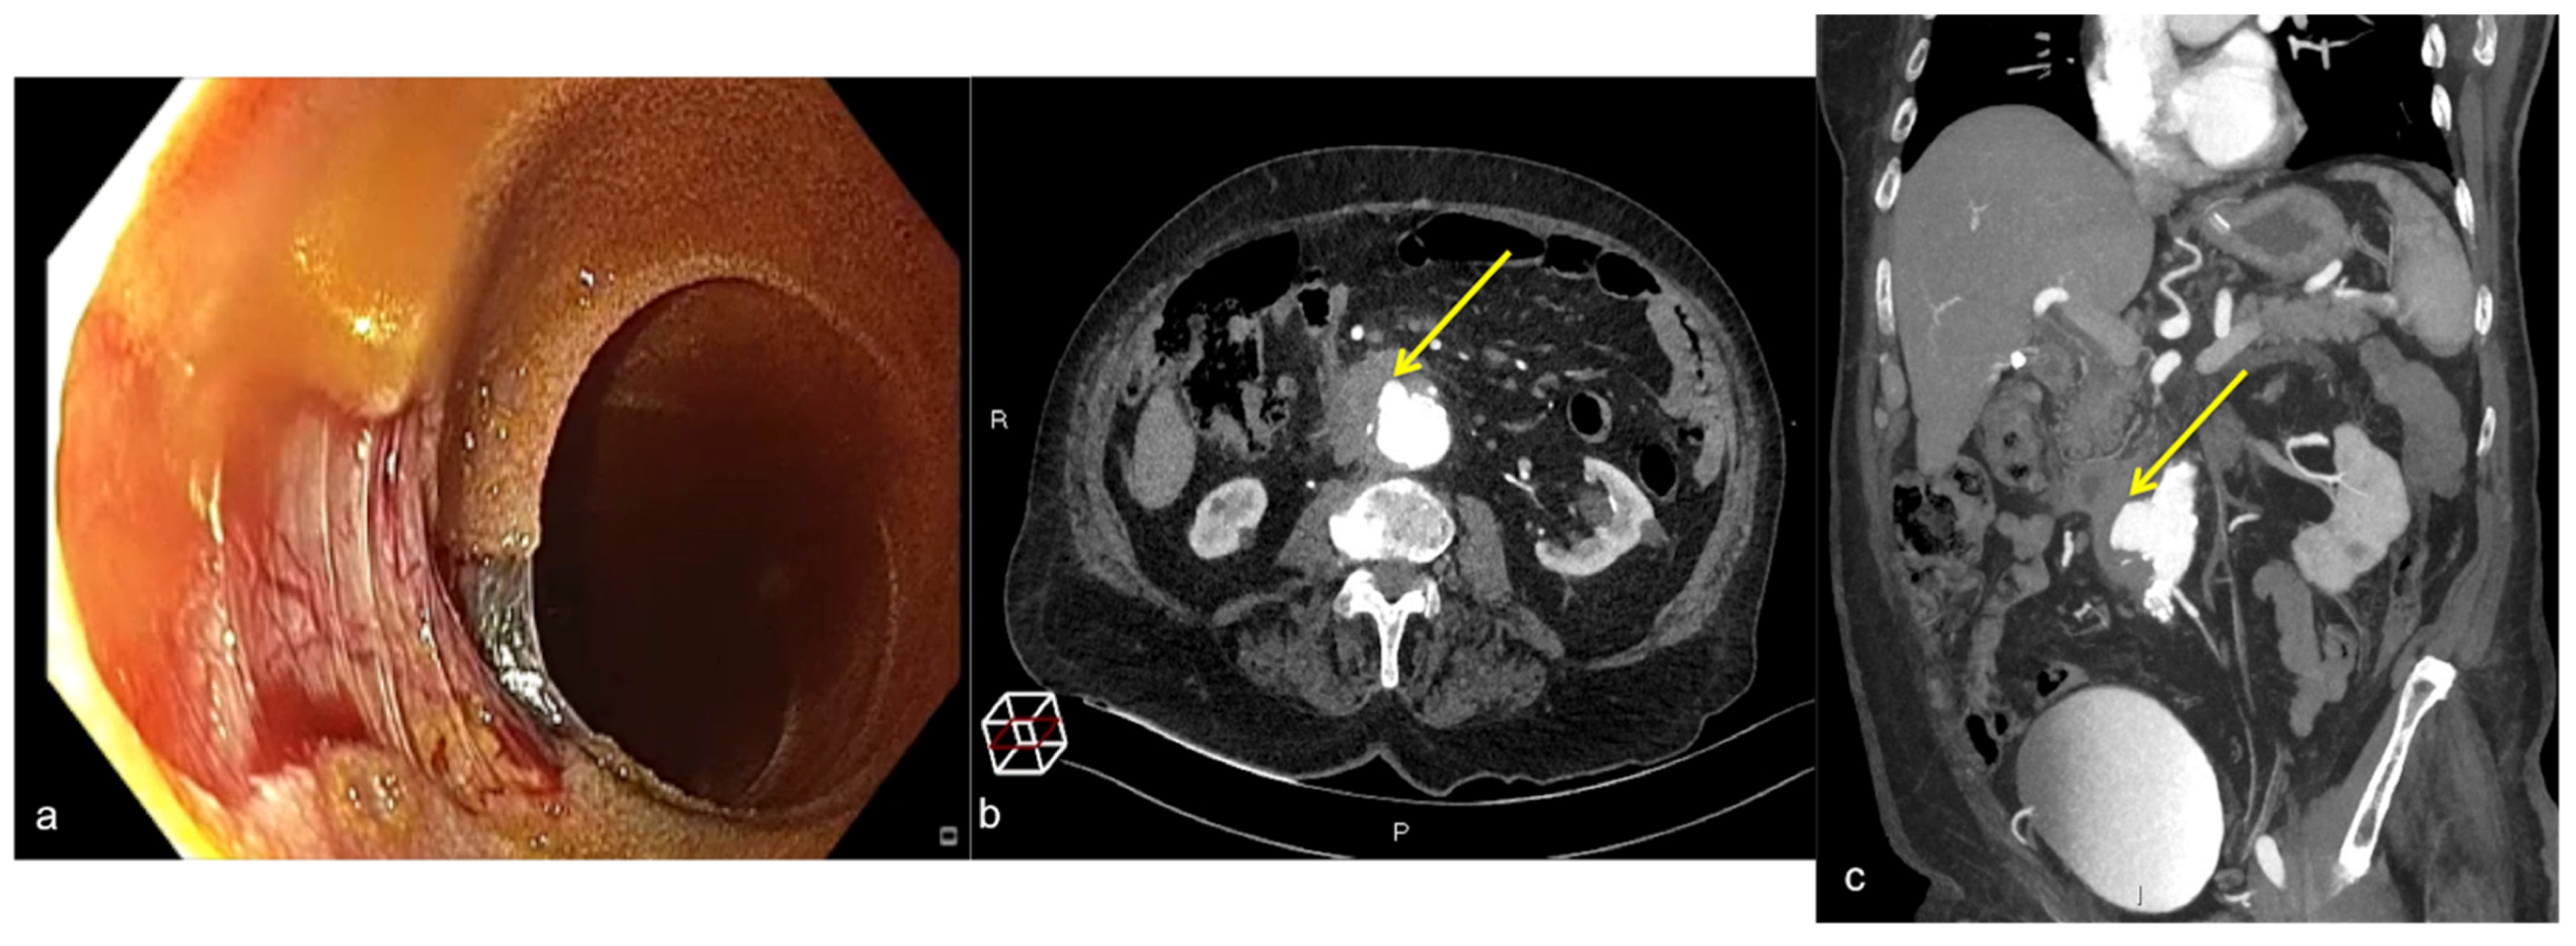

| Aorto-Enteric Fistula (Figure 31) | Bleeding in a patient with a history of surgery for aortic aneurysm. | A connection between the aorta and the intestinal lumen. Absence of adipose cleavage planes. |